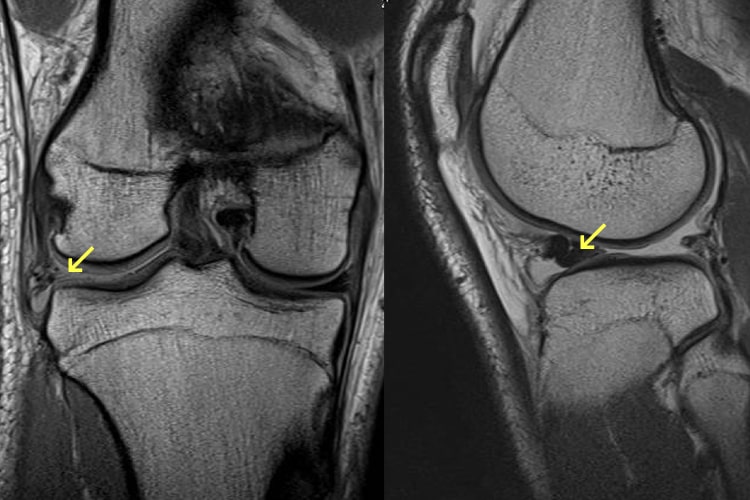

外側半月板損傷写真

外側半月板損傷

半月板損傷は膝関節の屈伸と回旋との協調運動が破綻した時に発生します。原因はスポーツ外傷によるものが多く、その他では転倒、捻挫、交通事故等があります。損傷によって、膝の曲げ伸ばしの際に痛みやひっかかりを感じたりします。ひどい場合には、膝に水(関節液)がたまったり、急に膝が動かなくなる“ロッキング”という状態になり、歩けなくなるほど痛くなります。治療としてはリハビリテーション療法、膝サポーター、ステロイド、ヒアルロン酸の関節内注射等、保存的治療での症状改善を目指します。保存的治療で改善しない場合には手術を行います。手術法には切除術(損傷した部分を切り取る)と縫合術(損傷した部分を縫い合わせる)の2種類があり、症状に合わせて選択します。